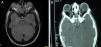

Casos clínicosEl caso 1 es un varón con gestación sin incidencias, parto a término con un peso de 2.890g, periodo neonatal, desarrollo ponderoestatural y psicomotor adecuados normales. Controlado en otorrinolaringología desde los 3 años por hipoacusia bilateral de transmisión con OMA de repetición. A los 511/12 años, acude al servicio de urgencias por proptosis ocular bilateral aguda tras episodio de vómitos de repetición y fiebre en contexto de cefalea de 2-3 semanas de evolución. En la exploración física y neurológica destaca exoftalmos bilateral y edema de papila bilateral. Se realizan radiografía y tomografía computarizada (TC) craneales, con aumento de densidad ósea generalizada, protrusión ocular izquierda con efecto masa intraorbitario dependiente del techo orbitario y elongación de ambos nervios ópticos. En la resonancia magnética (RM), se observan masas redondeadas intra y extraconales bilaterales de predominio izquierdo con efecto masa sobre músculo recto superior, diagnosticándose de encefalocele frontoorbitario izquierdo (fig. 1A y B). Como antecedentes familiares destaca el fenotipo materno: exoftalmos, prognatismo mandibular con ensanchamiento e hipoplasia malar.

A y B) Imágenes de TAC y RM, en (A) se aprecia un aumento de densidad ósea generalizada, protrusión ocular izquierda, con efecto masa intraorbitario dependiente del techo orbitario y elongación de ambos nervios ópticos; y en (B) se aprecia masas redondeadas intra y extraconales bilaterales de predominio izquierdo, con efecto masa sobre músculo recto superior (encefalocele frontoorbitario izquierdo).